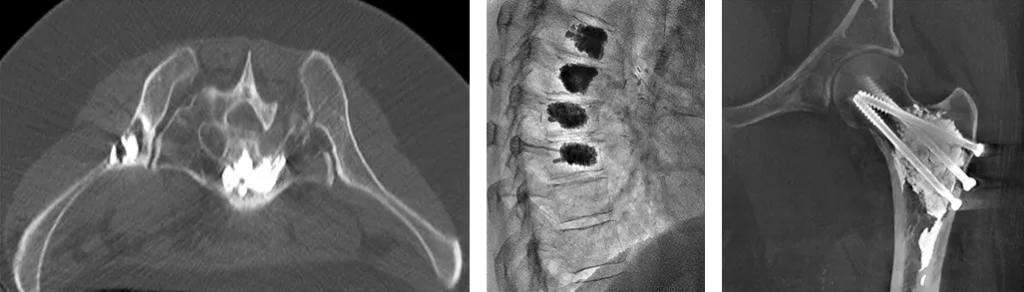

Figure 1 : technique de consolidation de lésions osseuses en radiologie interventionnelle

Exemples d’ostéosynthèse cimentée du bassin, vertébroplastie multiétagée et ostéosynthèse cimentée du col fémoral